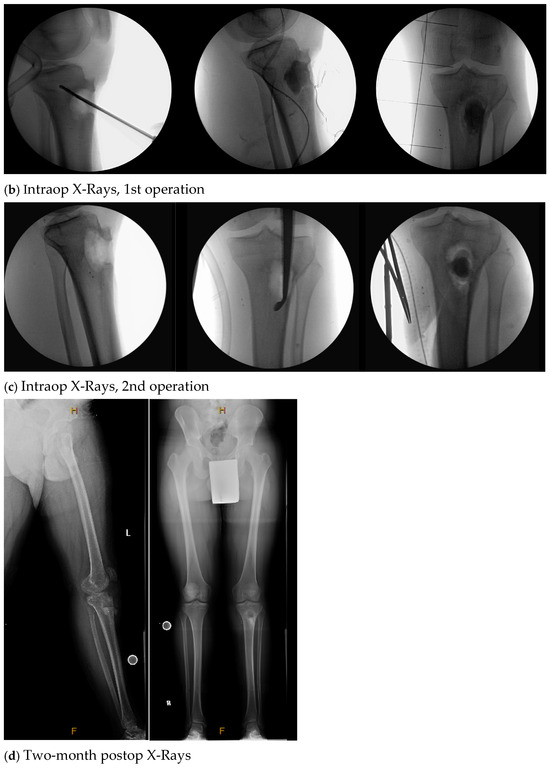

| 7. | N | Y (3) | 3 | <1 | Y, clinical and lab | 272 | 1st Op: Staphylococcus aureus, Klebsiella (Enterobacter) aerogenes 2nd Op: Negative |